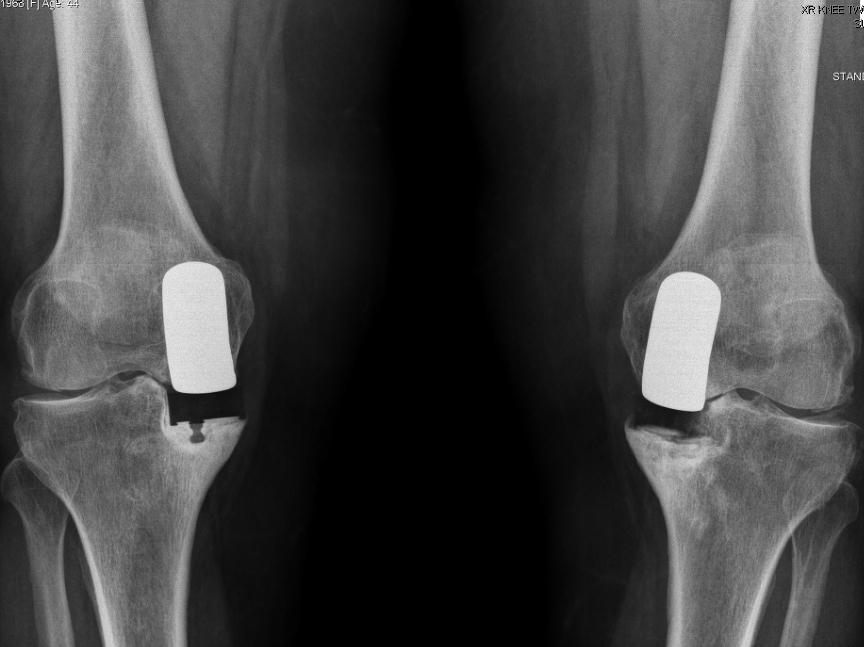

From www.researchgate.net

Longleg radiographs demonstrating bilateral medial How Long Does A Unicompartmental Knee Replacement Last The surgeon makes a small incision in the front of the knee and examines the three compartments of the knee joint. Most of our partial replacement patients are able to head home within a day or two days of their operation. A previous analysis of the finnish arthroplasty registry provided an estimate of the survival of total knee replacement at. How Long Does A Unicompartmental Knee Replacement Last.